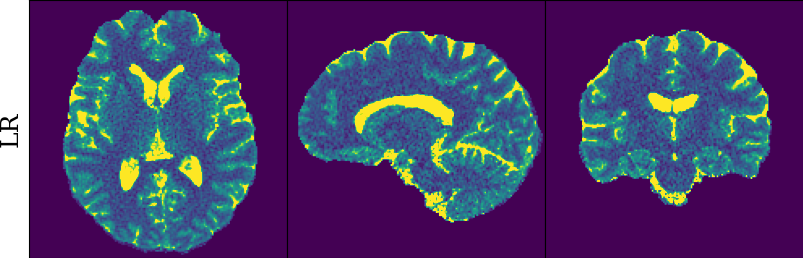

To monitor performance progress, we mapped TSMI to Q-Maps every five epochs. To mitigate the lengthy processing times associated with Dictionary Matching, we implemented a fully connected network to directly map TSMI to Q-Maps [5], significantly reducing processing time. However, for the final assessment, we employed DM on all techniques at the conclusion of the training process (epoch 500). We report in Table 1 the Mean Average Percentage Error (MAPE) of T1/T2 maps, and Peak Signal-to-Noise Ratio (PSNR) and Structural Similarity (SSIM) Index for T1/T2 and normalised PD. To accompany these metrics we also offer in Fig. 2 the reconstructed T1 and T2 maps for the different approaches.

The training and validation loss (Fig. 1) served as valuable guides for architecture and training design. To demonstrate this, we selected a subset of experiments in which we kept certain variables fixed and only modified the one under inspection. From Fig. 1 (a)-(d), MAPEs curves show there is a clear setting with the preferred performance. Specifically, from Fig. 1a, it is evident that using DRUNet yields a clear improvement over the original architecture. This could be attributed to the utilisation of residual units in addition to other architecture differences, such as the choice of upsampling operator (transpose convolution for DRUNet and trilinear for DIP). The choice of input (Fig. 1b) demonstrated a consistent pattern among the tested options, with low rank (conjugate gradient) initialiser marginally outperforming the others. Fig. 1cshows that by epoch 100, stochastic approaches exhibit lower reconstruction errors compared to non-stochastic methods. For example, adaptive LR with stochastic training yields a combined MAPE of 61.40% (17.09% T1 and 44.31% T2) vs. 213.69% (35.50% T1 and 178.19% T2) for the non-stochastic method. This fast convergence is due to adaptive LR and stochastic updates across coils. Despite similar execution times ( 34 min for stochastic with adaptive LR vs. 32 min for non-stochastic with fixed LR), the rapid error reduction makes StoDIP more attractive for training.. To assess the early stopping of DIP models, a key element, we present Fig. 1d. The original work by Ulyanov et al. [21] used 2k iterations, while Hamilton et al. [12] used 30k. In contrast, our settings show StoDIP achieving competitive performance in under 500 epochs (4k iterations) on the entire volume. However, StoDIP can overfit to k-space measurements, affecting reconstruction accuracy, and thus the iteration at which it stops could have a greater impact. We show that adding a spatial penalty term addresses overfitting and instabilities. This is supported by the maps in Fig.2, supplementary material Figures 1-3, and metrics in Table 1. StoDIP reconstructions lack aliasing artifacts, and the TV regularizer (StoDIP + TV) further improves Q-Map reconstruction by reducing checkerboard artifacts observed in StoDIP outputs alone.